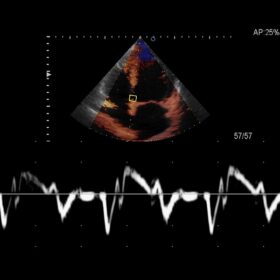

Ultrasound ARIETTA V60 – Image Gallery and Videos

Cardio 2D, Color, PW, CW and TDI mode

- Hitachi ARIETTA V60 is equipped with easy-to-use tools for comprehensive cardiac exams: Dynamic Slow-motion Display is a side-by-side presentation of a real-time image and its slow-motion counterpart. Dual Gate Doppler allows observation and measurement of Doppler wave forms from two separate locations during the same heart cycle. These advanced functions can shorten exam times and support effective investigations.